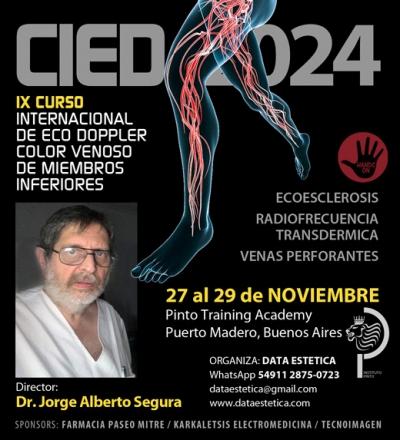

Capacitación | CIED 2018: 28 y 29 de noviembre

Flebología: adelantos de la nueva edición del Curso Internacional de Eco Doppler

Dirigido por el Dr. Jorge Alberto Segura, el CIED 2018 ya tiene fecha confirmada: la segunda edición del Curso Internacional de Eco Doppler color venoso de miembros inferiores se llevará a cabo el 28 y 29 de noviembre próximos en la Universidad de Belgrano, en Buenos Aires.

Dirigido por el prestigioso doctor Jorge Alberto Segura, reconocido académico y uno de los grandes especialistas en la materia, este segundo curso contará, como en su edición anterior, con relevantes disertantes invitados y con el auspicio de las empresas Karkaletsis Electromedicina, Laboratorio Cetus y Farmacia Paseo Mitre.

Dirigido por el prestigioso doctor Jorge Alberto Segura, reconocido académico y uno de los grandes especialistas en la materia, este segundo curso contará, como en su edición anterior, con relevantes disertantes invitados y con el auspicio de las empresas Karkaletsis Electromedicina, Laboratorio Cetus y Farmacia Paseo Mitre.Objetivos y destinatarios

La finalidad del CIED es poner al día los conceptos básicos de la Ecografía Doppler aplicados al estudio de la enfermedad venosa crónica y su utilización en la realización de distintos tratamientos endovasculares venosos, tales como Ecoesclerosis o Escleroterapia Guiada con Ecografía (líquida y espuma o foam), Láser Endoluminal Ecoguiado y Radiofrecuencia Endoluminal Ecoguiada; así como también de las más modernas técnicas de Glue o Moca.

El curso está dirigido tanto a los flebólogos, en particular, como a los médicos, cirujanos o no, que realizan flebología en su práctica clínica y desean tener un entendimiento de la enfermedad venosa a través de esta maravillosa herramienta.

También a aquellos médicos que hacen diagnóstico por imágenes y a todos los especialistas en general que quieran saber cómo se interpreta la enfermedad desde los ojos de un flebólogo.

La intención es demostrar cuáles son los datos y los elementos básicos que necesita todo flebólogo o médico que practica la especialidad.

En ese contexto, la correlación Clínico-Ecodoppler de la enfermedad venosa crónica es, en definitiva, el objetivo final de la realización de este II Curso Internacional de Eco Doppler color venoso de miembros inferiores.

Director del Curso: doctor Jorge Alberto Segura

- Evento: CIED 2018 / II Curso Internacional de Eco Doppler color venoso de miembros inferiores.

- Fecha: miércoles 28 y jueves 29 de noviembre de 2018.

- Sede: Auditorio Villanueva, Universidad de Belgrano: Villanueva 1324, Buenos Aires.

- Disertante a cargo: doctor Jorge Alberto Segura.

- Auspician: Karkaletsis Electromedicina, Laboratorio Cetus y Farmacia Paseo Mitre.

- Organiza: International Medical Training.